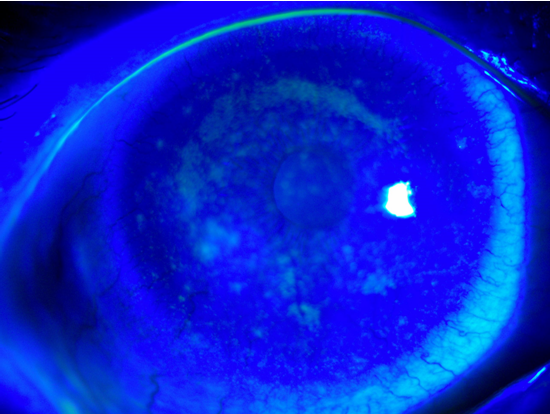

据深圳市第三人民医院消息,近日,在广东深圳,90后女孩小荆(化名)到医院检查后发现,自己的眼角膜上“爬满”了新生血管。 据了解,高度近视的小荆已经戴了10年的隐形眼镜,从早上出门上班,到晚上回家卸妆洗漱,每天戴隐形眼镜的时间几乎都长达10个小时。 就在上周她突然感到眼睛刺痛,还出现眼红、眼干、畏光。以前出现这种情况停止佩戴就能恢复,但这次却没有好转,于是来到医院就诊。 经检查,眼科主任医师发现—— 小荆的眼角膜不仅出现了水肿、缺氧的情况,还“爬满”了大量新生血管; 双眼睑缘红肿,结膜充血; 睑板腺开口部分堵塞,油脂污浊; 角膜散在大小不等的白色病灶,荧光素染色可见弥漫染色。 以上症状如果不引起重视,对眼睛有极大的危害。 眼睛不同于其他器官,眼睛角膜,也就是即我们目视前方看到的“黑眼珠”的表层,角膜上是没有血管的,所需要的氧气都来自于空气的渗透。 新生血管是由于组织发生炎症,缺血缺氧导致血管内皮生长因子的大量释放,产生的坏血管。 这些坏的血管可以从角膜边缘开始,蔓延到角膜中央,角膜新生血管有时会伴有角膜上皮细胞的脱落,甚至是角膜溃疡。 所以一旦产生了这些新生血管可能会引起很严重的后果,甚至造成失明。 对于常年配戴软性隐形眼镜的人群,如果变得越来越不耐受隐形眼镜,黑眼圈周边出现红血丝,那么您需要看眼科医生、筛查【角膜缘干细胞缺乏】。 它是一种被忽视的疾病,由于角膜缺氧导致角膜缘干细胞死亡,患者表现为视力下降、畏光、眼睛疼痛。严重的角膜缘干细胞缺乏患者,需要做干细胞移植手术。戴软性隐形眼镜、超长时间配戴(例如每天>10小时)、女性是危险因素[1]。 隐形眼镜可能对角膜的危害之一就是因为透氧性不足可能会导致角膜缺氧、产生新生血管,新生血管会往瞳孔蔓延最终影响视线。 其次很多人觉得隐形熬夜不摘也无所谓,甚至一直不摘也没什么,结果就可能造成隐形眼镜与角膜粘连,强行摘除会导致角膜上皮严重损伤。 现在大家用眼过度,眼干疲劳是经常事,于是为了缓解疲劳,使用一些所谓抗疲劳眼药水、清凉眼药水、尤其是某品牌 FX 眼药水等等。 偶尔使用可以,长期使用不仅无法缓解症状,甚至会加重眼干、疲劳感。 一些眼药水使用不当更有可能造成诱发青光眼、干眼症等严重后果。 相信这个习惯大多数人都有,睡前不玩手机睡不着,但是关了灯玩手机短波蓝光的直射更强,可能会造成视疲劳、干眼症甚至也会诱发青光眼。 眼睛是我们最脆弱的器官,在日常生活中很多看似正常的习惯、光线,正在不知不觉的侵害我们的眼健康,可能稍不留意就会导致眼睛不可逆的损伤。 瑞士原装进口TESLA量子超光眼镜能调节外来光线(过滤紫外线和短波蓝光,保留有益的蓝光,同时加强黄光、橙光、红光等有益光),采用诺贝尔奖新材料富勒烯C60,让通过的光线以180亿次/秒的旋转扭曲频率,使通过的光线更安全快速的帮助调理眼睛健康。 TESLA量子超光眼镜,能有效缓解眼睛干涩、酸胀、视物模糊等症状,有效保护视力,预防调理眼疾病。 让每天进入我们眼睛的光线都是安全的! 【参考文献】

戴隐形眼镜人群,如果眼睛出现并发症,7.9%也会出现角膜新生血管[2]。根据韩国的研究[3],高度近视、高度散光、角膜曲率陡的患者,戴水凝胶材质的软性隐形眼镜更容易出现角膜新生血管。